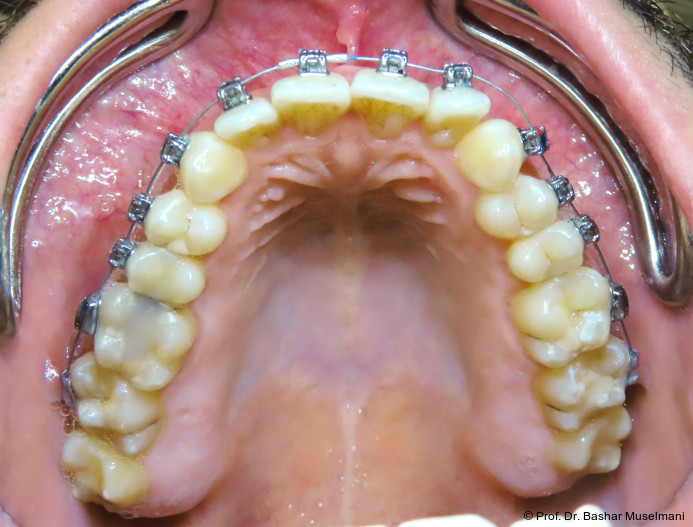

Apparative Versorgung

Die Behandlung erfolgte mittels einer festsitzenden Multibracketapparatur unter Verwendung passiver selbstligierender Brackets (Damon Ultima System) im Ober- und Unterkiefer.

Die Wahl des Systems erfolgte mit den Zielen,

• die Torque-Expression effizient auszuschöpfen,

• eine kontrollierte dentoalveoläre Kompensation zu ermöglichen,

• unerwünschte Nebenwirkungen während der Klasse III-Korrektur zu minimieren.

Zur sagittalen Korrektur wurden intermaxilläre Klasse III-Gummizüge eingesetzt.

Bracketpositionierung und Torque-Strategie

Oberkiefer

• Zähne 12–22: Brackets mit Retroklinations-­Torque

• Zähne 13 und 23: Brackets mit proklinationsförderndem (Brocline-)Torque

Ziel war die kontrollierte Retrusion der oberen Front bei gleichzeitiger Sicherung der Eckzahnbreite.

Unterkiefer

• Zähne 33–43: Brackets mit proklinationsförderndem Torque

Hierdurch sollte eine gezielte Proklination der unteren Front zur Verbesserung des Overjets und der sagittalen Verzahnung erreicht werden.

Zu Beginn der Nivellierungsphase wurden in beiden Kiefern 0.013" CuNiTi-Bögen eingesetzt (Abb. 4a–e).